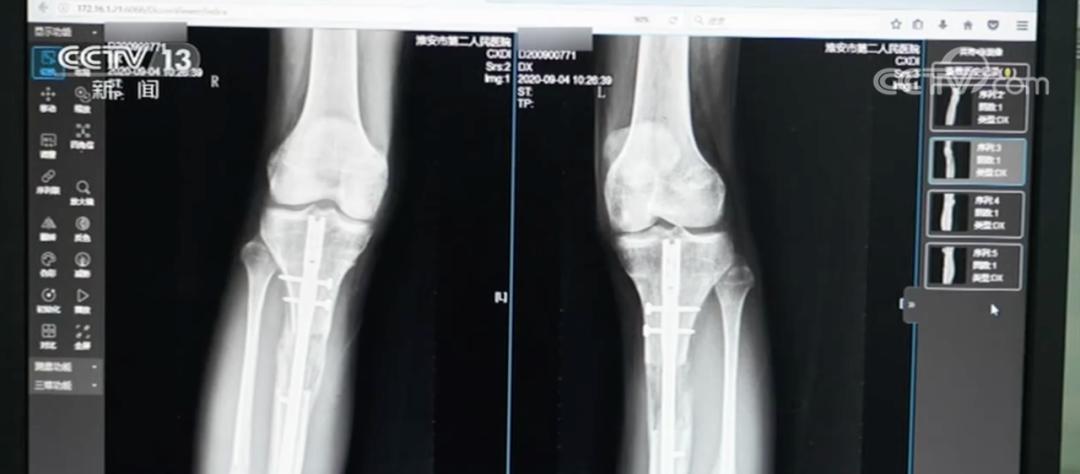

外架手術需要截斷腿骨,用鋼針穿透皮膚肌肉固定斷骨,外部用圓環加固。術後每天需要調整支架旋鈕拉伸雙腿,全程需要一年半時間。內置手術則是沿腿骨植入電磁驅動髓內延長釘,通過體外遙控牽引,術後僅留2釐米微小疤痕且恢復期只有3個月時間。

然而,令小夢沒想到的是,在術後第六個月,併發症突然來襲。小夢右小腿斷骨處出現紅腫潰爛,膿液不斷滲出,被確診爲急性骨髓炎。此時,梁某還威脅她只有在羣裏說好話,才能接受後續安排的治療。

如今,她體內的髓內釘至今仍未取出,因爲取出手術可能引發二次骨折。更令她擔憂的是,內置物中的磁鐵成分可能會生鏽,內固定裝置還有斷裂風險,小夢直言:“就像有顆定時炸彈藏在身體裏”。

雖然小夢後續在國內接受了X型腿矯正手術,但效果並不理想。“我的腿腳經常痠疼,走路時間長了就會感到疲勞和僵硬,就像腿上綁着沙袋一樣,斷骨處也很疼,我不能像正常人一樣起身、蹲下。”